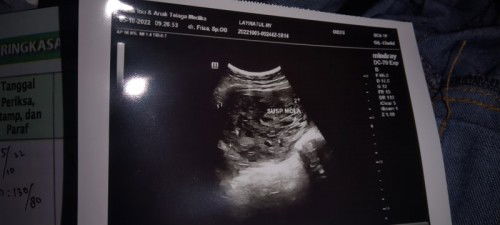

Flek di trimester pertama ternyata hamil anggur (yg aku AlAmin)

Sangat sedih rasanya mengetahui ternyata hamil anggur,, dan itu baru tau diusia kandungan 13w ,, gejalanya tidak bisa di bedakan antara hamil yg ada janinnya dan tidak,, 1x diusg ternyata hamil anggur dan harus langsung dikurret karena hamilnya udah mau nginjak trimester2,, GK fikir panjang langsung kurret aja GK USG LG di tempat lain soalnya USG nya udah kelihatan bgt kalo GK ada janinnya dan setiap sore menjelang malam perut rasanya sakit bgt jadi langsung aja tindakan kurret ,awalnya takut banget dikurret tapi ini demi kesehatan kalo GK dikurret nanti bisa jadi kista kata dokter,,dan aku pengen hamil lagi dan saat ini lagi pemulihan,, mungkin belum saat nya anakku jadi kakak.. untuk yg lagi hamil sehat2 ya semoga lancar sampe persalinan... Semangat bunda2 #hamilanggur #kurret